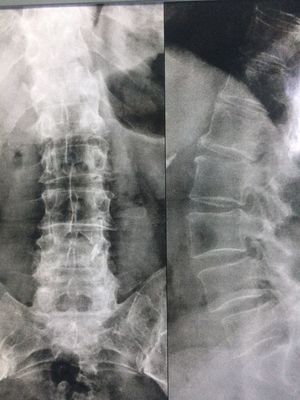

Female, 62 years old, retired. She has chronic low back pain that worsens with movements and overload. Observing the radiograms what are the 3 main visible alterations?

Scoliosis , degeneration ,L4 L 5 displacement, pot spine vertebrae